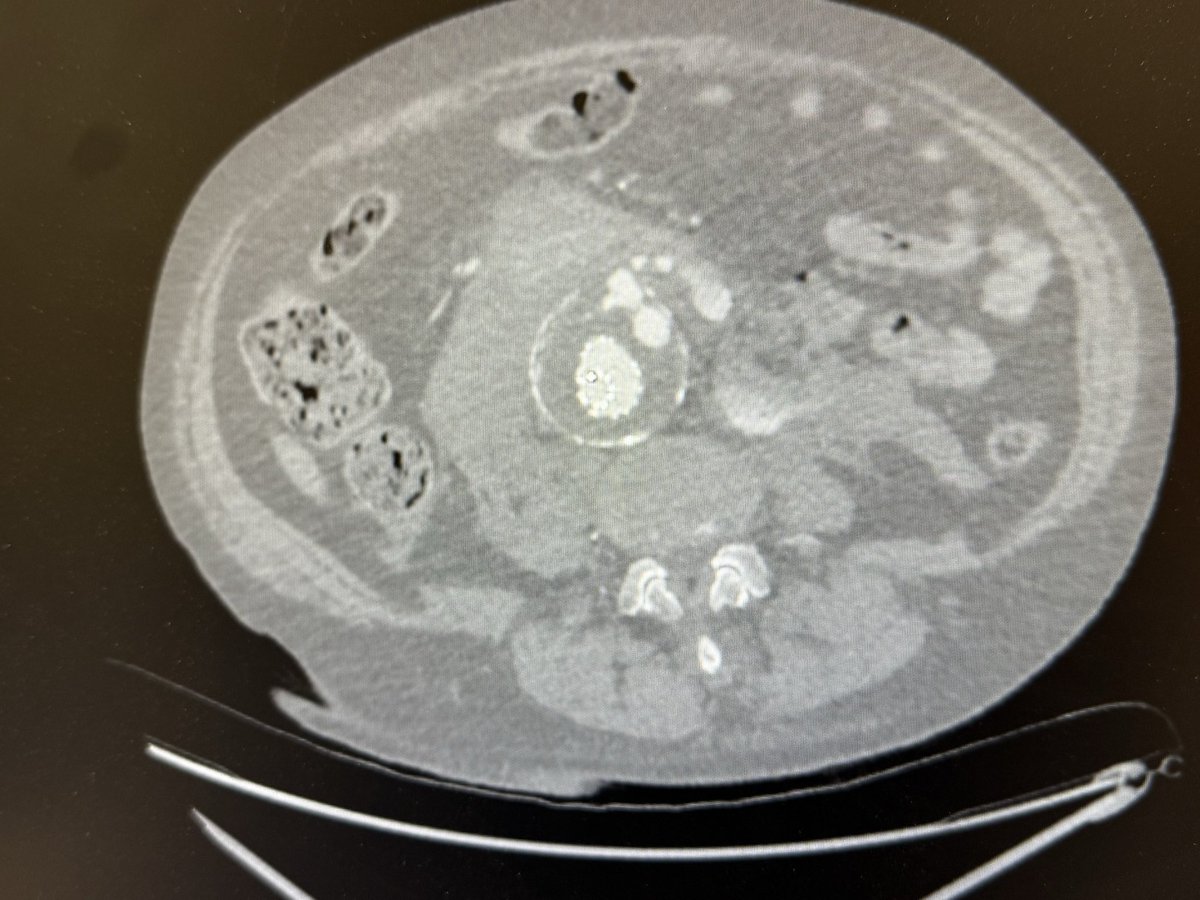

Diagnosis : Popliteal artery entrapment syndrome causing acute limb ischemia Intra-op pictures

#vasctwitter 17 yrs old male, keen football player.sudden onset pain in right leg and foot. Absent foot pulses and pale foot. CTA below. What is the diagnosis? Look at cross sectional image?! How would you treat?